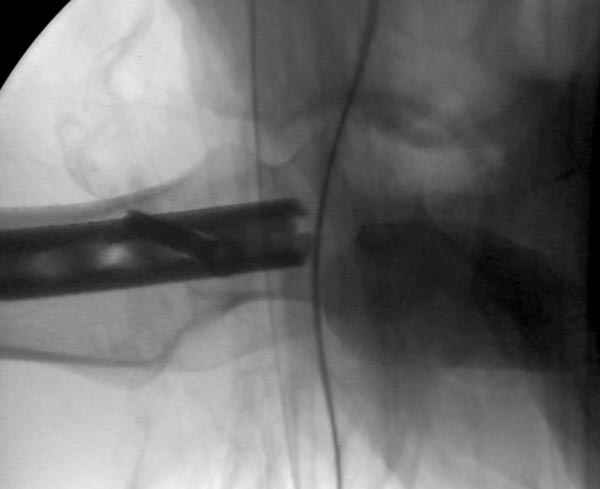

Второй случай тоже репозиция из малого доступа, больному 19 лет, множественные огнестрельные повреждениия конечностей, живота и черепа, правая конечность холодная, без пульсации. Ортопедический диагноз: огнестрельный перелом правого бедра. При срочной ангиографии повреждения сосудов не подтвердилось, конечность из-за ургентности состояния больного зафиксирована временным наружным фиксатором и больной оставлен на операционном столе для срочной лапаротомии хирургической службой.

Больной долго оставался нестабильным, только на 14 день удалось заменить на антеградный интромедуллярный штифт TFN (trochanteric femoral nail) SmithNephew. После неудачной попытки закрытой репозиции, несмотря на использование "joystick", проксимальный стержень от

наружного фиксатора, (перелом начал срастаться) репозицию провели из малого доступа, затем остальные этапы операции.

Случай был представлен из-за того, что больного оперировали после наружной фиксации и был риск инфекцирования через места проведения стержней (на снимках), прошло больше 3 месяцев, выписан из амбулаторной службы из-за отсутсвия надобности дальнейшего наблюдения.